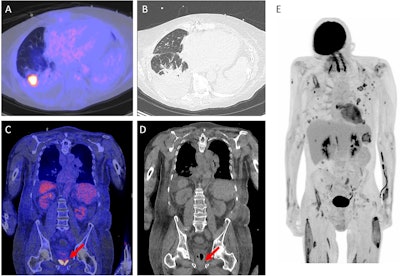

There are several conceivable advantages of F-18 FDG PET/CT over conventional imaging. Image A and B showing an example of the distinctive capability of the F-18 FDG PET/CT. A shows a fusion image of F-18 FDG PET/CT and low-dose CT and B an high resolution chest CT of a patient with an Aspergillus infection. The suspected aspergilloma is concealed on the high resolution CT due to the lung fluids and consolidation. Image C and D (fusion image of F-18 FDG PET/CT and low-dose CT and low-dose CT only, respectively) are examples of the ability to image inflammation while no concurrent abnormalities are visualized, in this case prostatitis (red arrows). Image E, a maximized intensity projection of F-18 FDG PET, shows a patient with lung infections and multiple muscle abscesses after MRSA sepsis. This is an illustrative example of a relevant dissemination investigation. Image and caption available for republishing under Creative Commons license (CC BY 4.0 DEED, Attribution 4.0 International) and courtesy of Annals of Intensive Care.